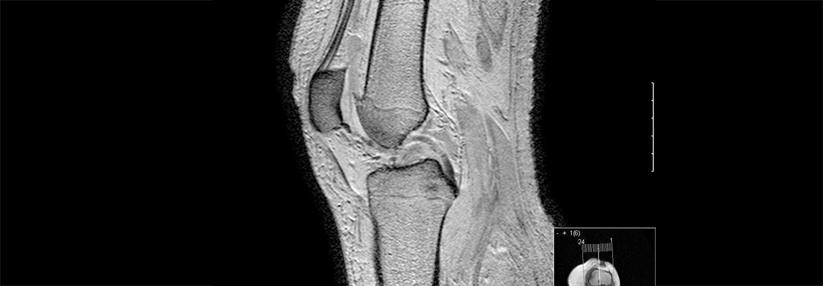

MRT

• Bei Diskrepanz zwischen klinischem und radiologischem Befund

• bei ausbleibender Besserung unter Standardtherapie

• Nachweis von Osteonekrosen

• Beurteilung von Weichteilgeweben und Knorpel (z.B. Labrum des Hüftgelenks)

• am Knie bei z.B. Meniskuszeichen, Kreuzbandinstabilität

• vor Arthroskopien